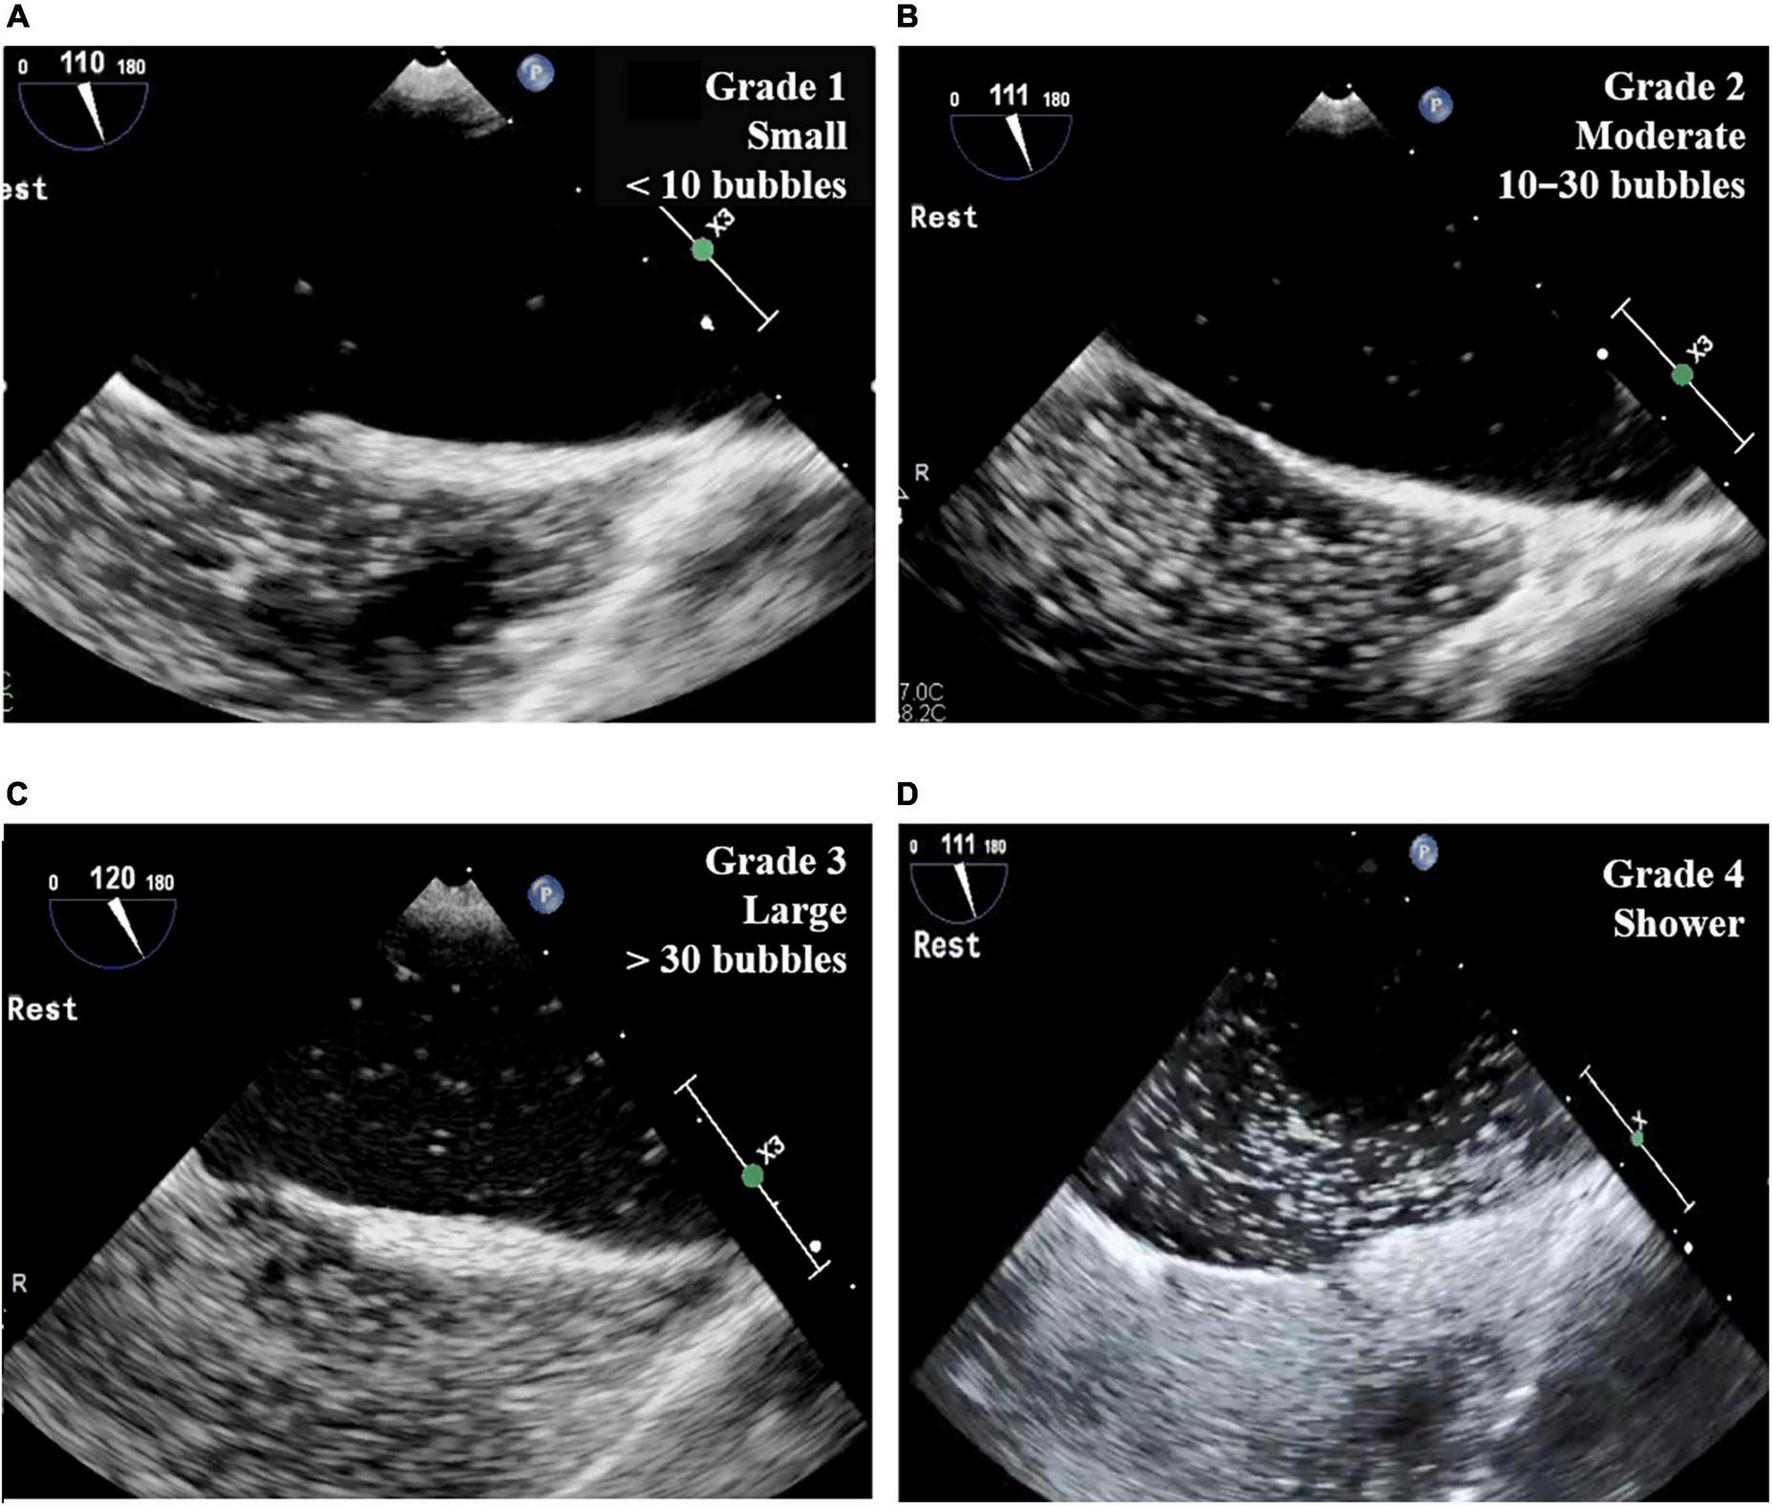

The two-dimensional and Doppler echocardiographic examinations were performed in a standard manner (18, 19) using commercially available echocardiographic devices. Standard TECE with the agitated saline test was performed in study patients by an experienced echocardiography specialist with the support of a sonographer. Three-way stopcocks with 10 ml syringes connected to both ends were placed in the patient’s forearm veins. The saline contrast was composed of 8–9 ml of normal saline agitated with 0.5 ml of air and a small amount of the patient’s blood. In the first study with each patient, the agitated saline contrast test was performed during rest in the bicaval view (110° view). The second test was performed with the Valsalva maneuver or coughing in the bicaval view or a 45° view. Then, the saline contrast test was performed without the Valsalva maneuver in the right and left pulmonary vein select view. In each test, the number of cardiac cycles was measured between the full appearance of air bubbles in the right atrium and their appearance in the LA. The number of bubbles and the location of the shunt were also recorded. The number of bubbles in the LA was graded according to a 4-grade system: grade 1, a small amount of contrast or fewer than 10 bubbles; grade 2, a moderate amount of contrast or 10–30 bubbles; grade 3, more than 30 bubbles; grade 4, a shower with extensive contrast in the LA (Figure 2). The TECE classification of shunt size was based on the grading system for patent foramen ovale (20), which was modified slightly to facilitate the evaluation of shunt size. Our grading system also differentiates the shower grade in accordance with the TTCE grading system, which is another screening test for diagnosing PAVMs (9).

FIGURE 2

Grade of TECE with agitated saline test. (A) Grade 1 (small): fewer than 10 bubbles in LA; (B) grade 2 (moderate): 10–30 bubbles in LA; (C) grade 3 (large): more than 30 bubbles in LA; (D) grade 4 (shower): extensive contrast in LA. TECE, transesophageal contrast echocardiography; LA, left atrium.